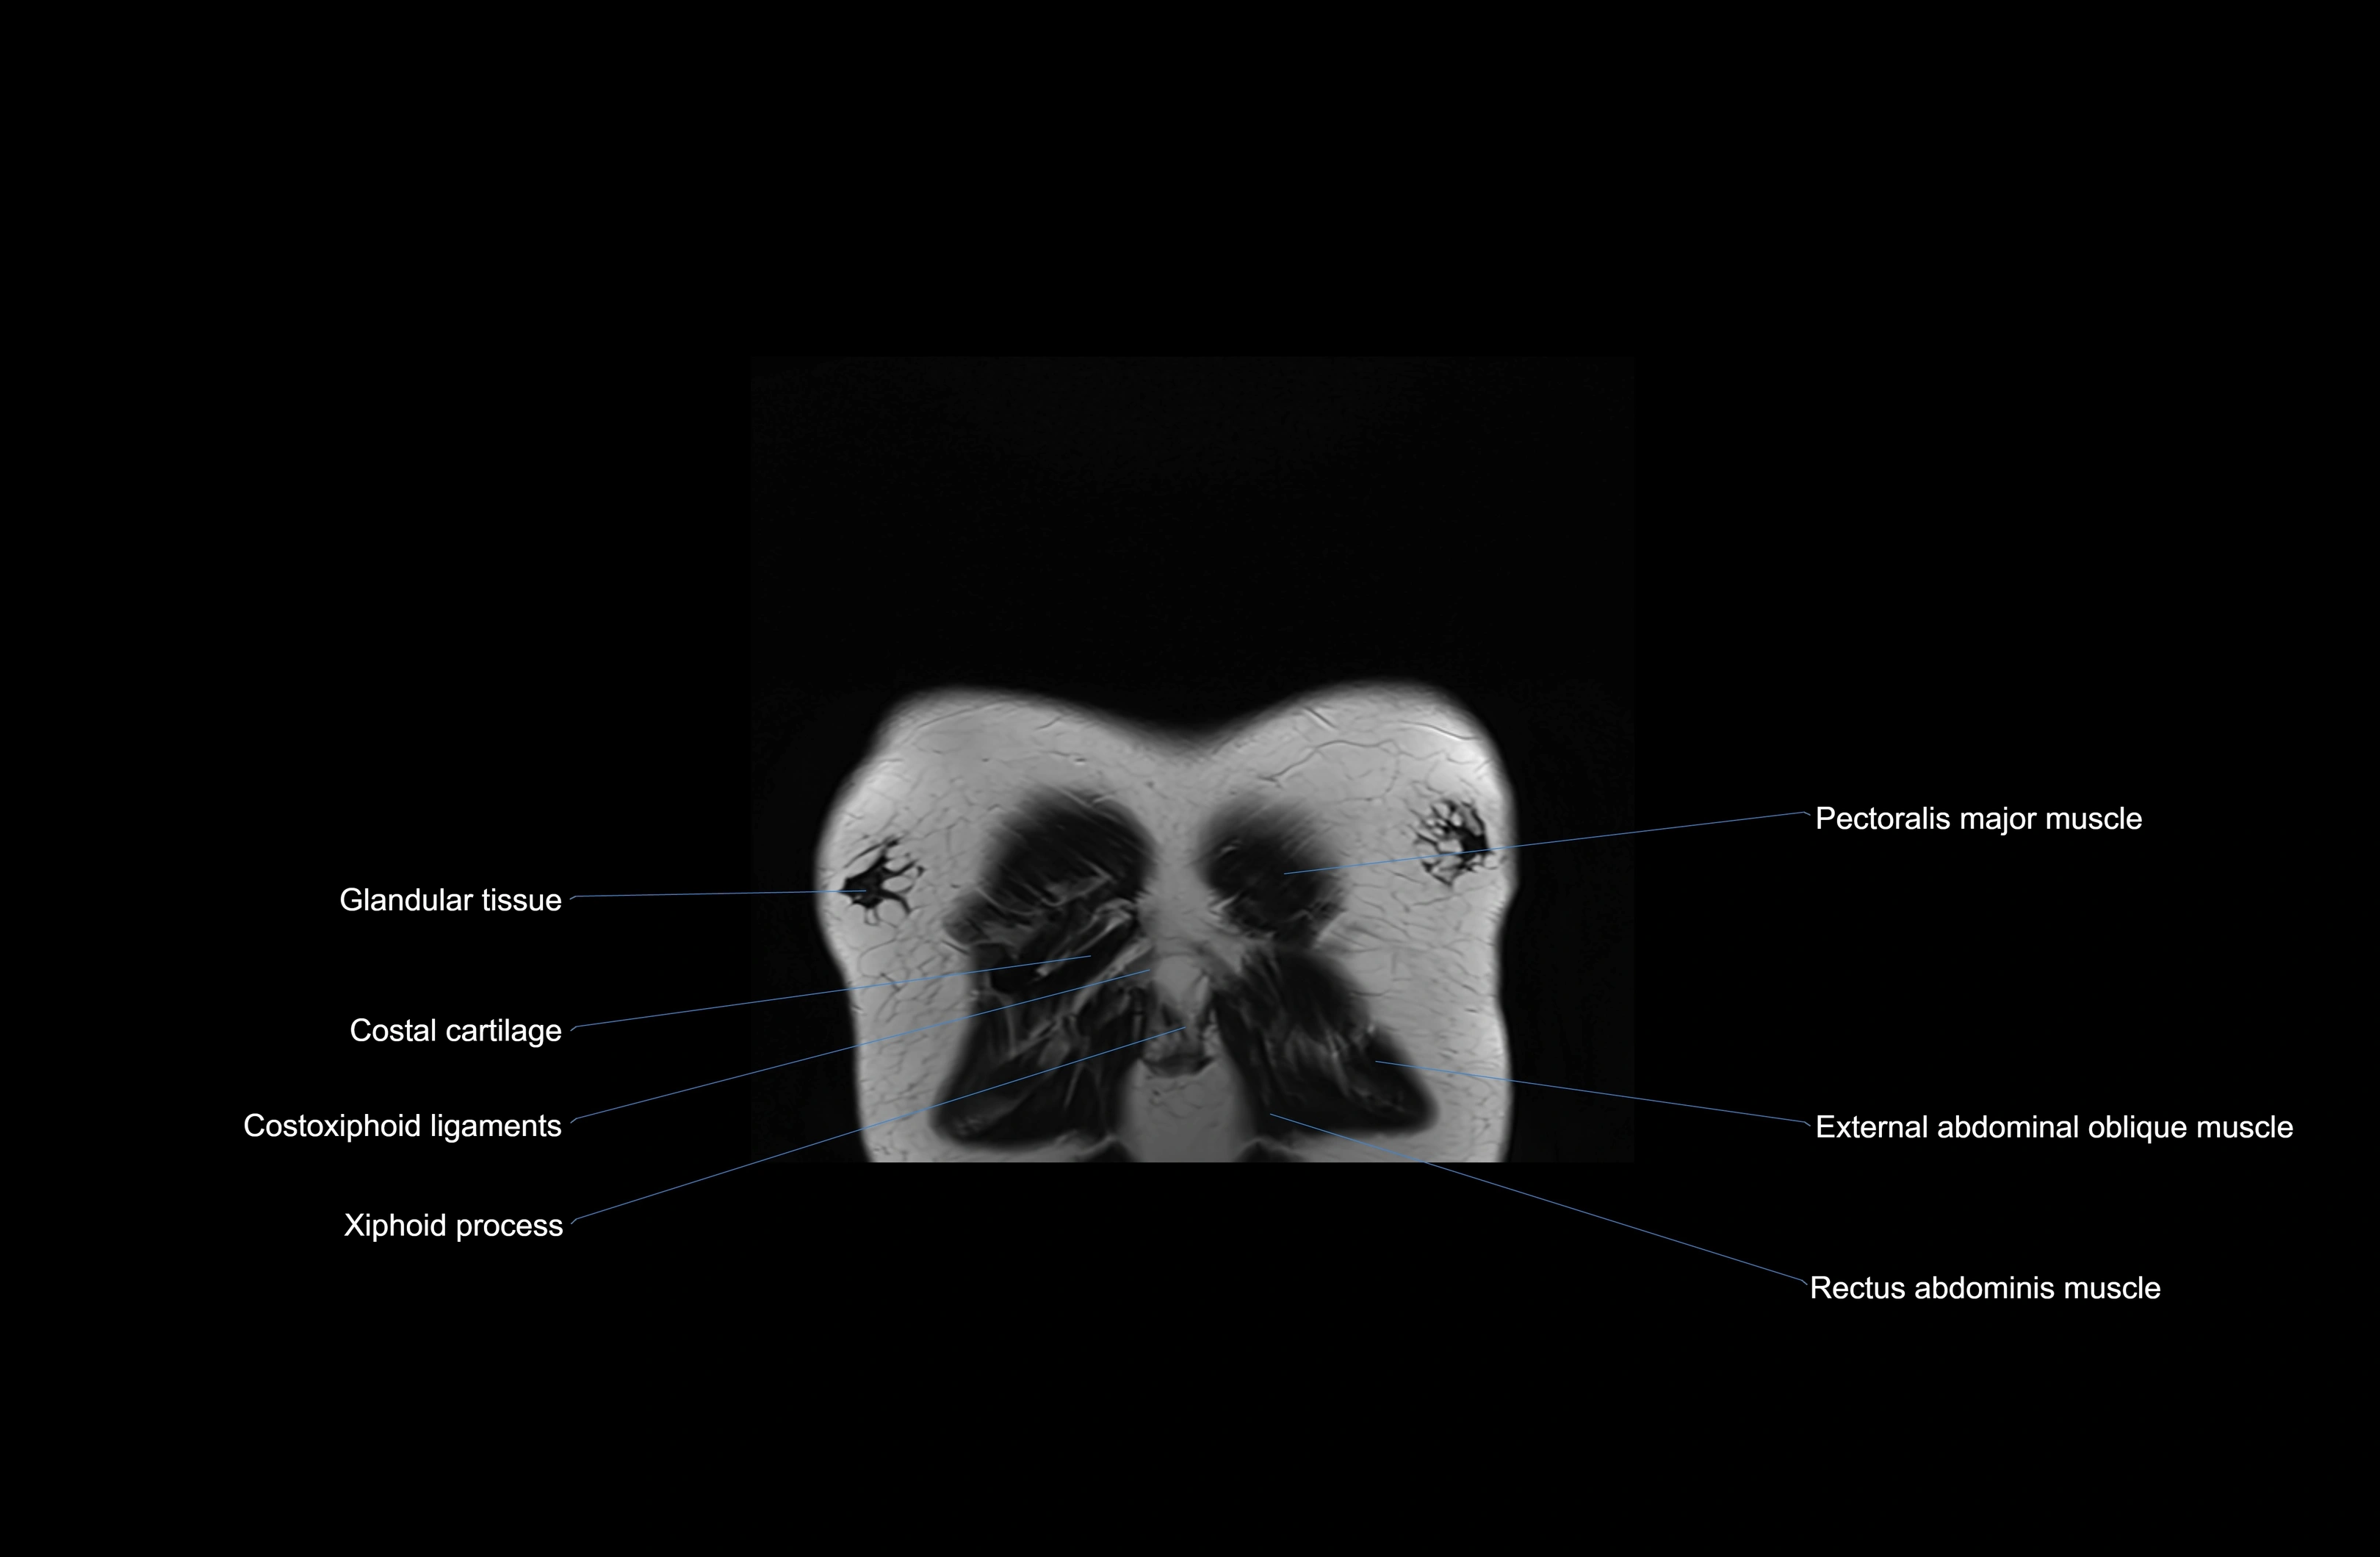

MRI images